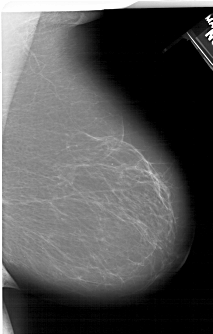

A_1406_1.RIGHT_CC

RIGHT_CC LINES 6871 PIXELS_PER_LINE 4051 BITS_PER_PIXEL 12 RESOLUTION 43.5 NON_OVERLAY